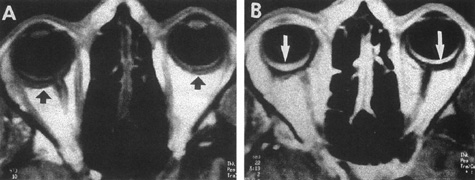

Fig. 3. Magnetic resonance images of intracavernous aneurysm in a 72-year-old woman with left retrobulbar pain and sixth-nerve palsy. A: Coronal section (TR, 800 ms; TE, 30 ms). B: Parasagittal section (TR, 1000 ms; TE, 20 ms). C: Axial section (TR, 800 ms; TE, 30 ms). Note partial occlusion by thrombus (T). D: In a similar patient, carotid arteriogram (subtracted, lateral view) demonstrates a large intracavernous aneurysm.

Intracavernous aneurysms are suspected by the clinical presentation of a chronic cavernous sinus syndrome and are diagnosed by enhanced computed tomography (CT), magnetic resonance imaging (MRI), and arteriography (see Fig. 3). Because of the location and configuration within the cavernous sinus, direct surgical approaches to cavernous carotid aneurysms are hazardous. In recent years intravascular occlusion of the internal carotid by detachable balloon has evolved as a safe and successful procedure, often with relief of pain and improvement in ophthalmoplegia.10 Unfortunately, these balloons are commercially unavailable at the time of this writing.